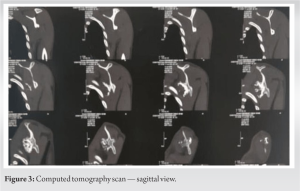

A 21-year-old man reported having a swelling over his left upper back region for the past 10 years, over which period it gradually increased in size. He had no other complaints. On examination, it was found that the overlying integument was normal, bony hard in consistency arising from the medial border of the scapula, non-tender, and approximately 7 × 7 cm in dimension. Moreover, winging of the scapula was observed, which was static as it did not increase with flexion of the arm against resistance. In addition, he had a complete range of motion without neurovascular compromise. Further assessments were conducted using roentgenography, computed tomography scan, and magnetic resonance imaging (Fig. 1, 2, 3, 4), through which two lesions were distinguished; a 70 × 55 mm exophytic tumor arising from the ventral wall of the body of the scapula directed posteromedially, scalloping the adjacent chest wall, and another similar lesion of 30 × 25 mm projecting laterally.